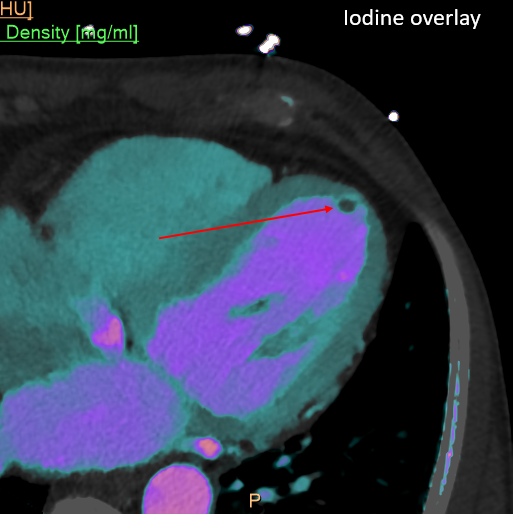

Attention to #spectral images! Gopal Punjabi ⚠️ The endobronchial content is enhancing --> solid! 1️⃣Virtual non-contrast (VNC)= 39HU 2️⃣Conventional= 71UH (>20UH compared to VNC) 3️⃣ Iodine density =1.26 mg/ml